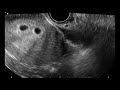

Однако, в ранние сроки беременности, физические признаки могут быть менее заметными, и некоторые женщины могут смочь скрывать беременность от окружающих. Обычно первые признаки беременности, такие как утренняя тошнота или отсутствие менструации, возникают через несколько недель после зачатия, но индивидуальные различия могут повлиять на появление признаков раньше или позже.